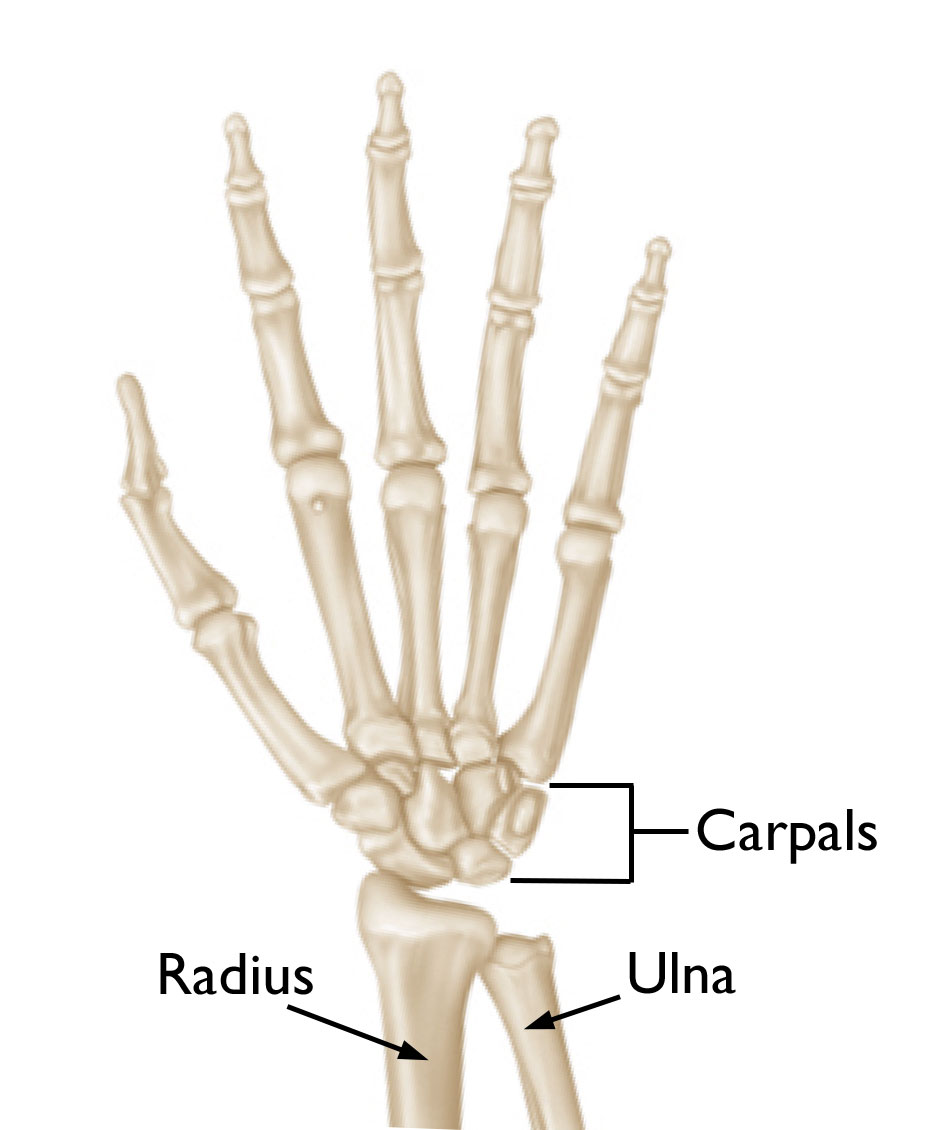

Anatomy

The wrist joint is a more complicated joint than the hip or the knee.

• On the hand side of the wrist, there are two rows of bones that connect the end of the forearm to the hand. These bones are called carpal bones, and there are four of them in each row. There is movement between the carpal bones during wrist motion.

• Past the carpal bones are the metacarpals, which sit on the last row of carpal bones, connecting the wrist to the fingers.

• The radius and the ulna are the two bones of the forearm. They form a joint with the first row of carpal bones that is important in flexing and extending the wrist.

• The radius, on the thumb side of the wrist, is wider at the wrist than the ulna and makes up most of this joint.

• The ulna, on the small finger side of the wrist, is narrower than the radius at the wrist.

• The joint between the radius and ulna, the distal radioulnar joint, is important in rotation of the forearm.

Illustration Showing the Bones of the Wrist

The bones of the wrist. Cartilage coats the ends of the bones to create a gliding joint.

Reproduced from JF Sarwark, ed: Essentials of Musculoskeletal Care, ed 4. Rosemont, IL, American Academy of Orthopaedic Surgeons, 2010.